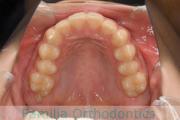

No.14V-516

- 主な症状:

- 上顎前突

- その他の症状:

- 叢生

- 年齢:

- 10歳

- 性別:

- 女性

- 抜歯部位

- 上:

- 44

- 下:

- 55

- 主な使用装置:

- FEA

- 治療にかかった費用:

- 90万円

きれいな歯並びにしたいということで来院されました。第一期治療で六歳臼歯の位置を維持する装置を入れて第二期治療の準備をしました。第二期は中学生になってから小臼歯を抜歯して行いました。二期治療は約2年半、25回程度の通院が必要でした。

二期治療開始前は叢生(でこぼこ、凹凸、ガタガタ)がかなりありましたので、保定をしっかりしないと段差ができてきたり後戻りのリスクがあります。